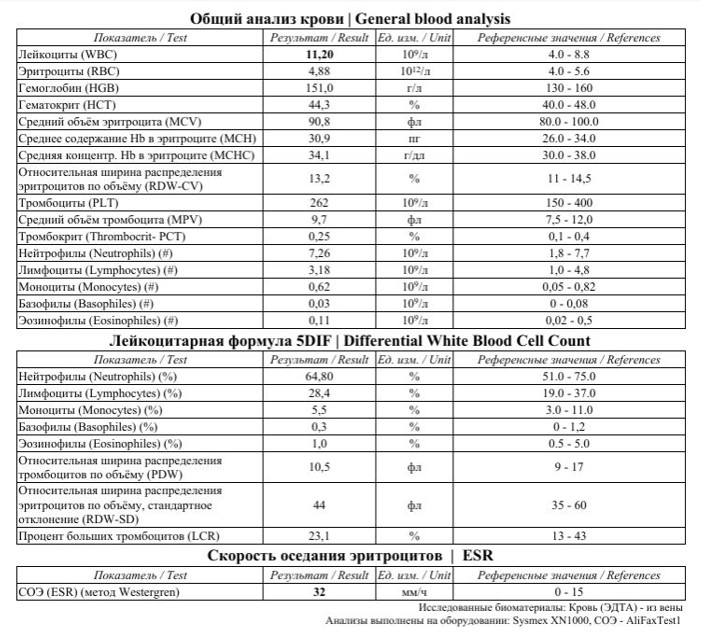

Лабораторное исследование крови. Общий анализ крови – ускорение СОЭ, что свидетельствует о воспалительном процессе.

В биохимическом анализе крови при рецидивирующих наружных отитах обязательно стоит обращать внимание на показатели глюкозы крови, так как рецидивирующие воспалительные процессы часто являются симптомом Сахарного диабета. У данного пациента глюкоза крови в норме, но отмечается повышение СРБ, что также свидетельствует о наличии воспалительного процесса в организме:

При повторных анализах крови в результате лечения (через 10 дней) отмечается нормализация показателей Общего анализа крови и СРБ, что свидетельствует о выздоровлении.